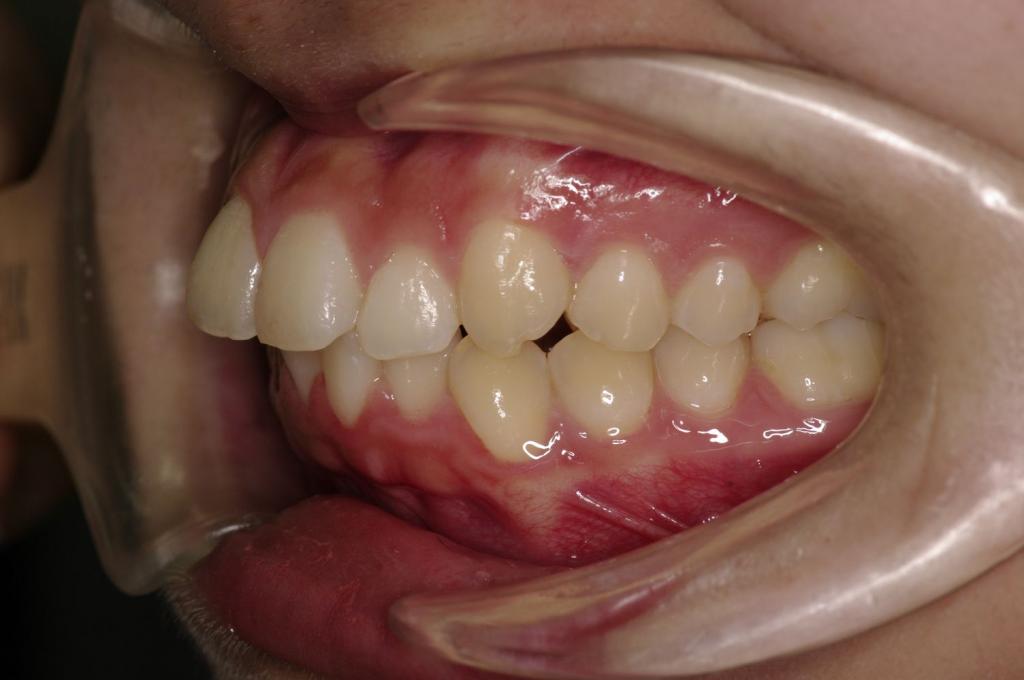

前歯、出っ歯・開咬の矯正治療

(治療期間、治療前後写真、治療方法、費用)WORKS